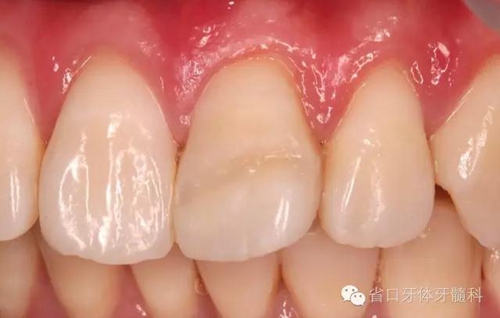

患者1個(gè)半月后復(fù)診,口腔衛(wèi)生狀況保持良好,牙齦健康,折斷線不可見(jiàn)。

斷冠再接優(yōu)勢(shì):快速恢復(fù)美觀,降低患者創(chuàng)傷后心理傷害,容易被患者接受;花費(fèi)低、操作簡(jiǎn)單。不適用粉碎性冠折,遠(yuǎn)期臨床效果有待進(jìn)一步觀察。